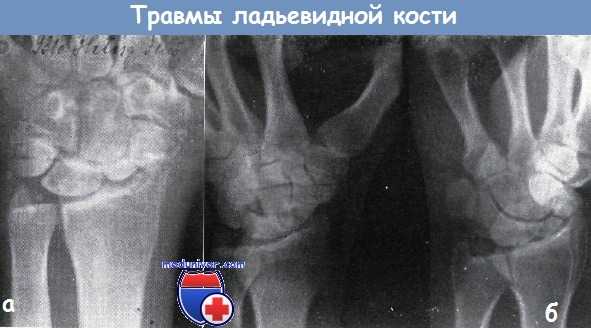

а - на рисунке представлен механизм перелома ладьевидной кости по Янику, при прямом падении на кисть, находящуюся в тыльном сгибании

б - механизм смещения отломков ладьевидной кости при движении кисти

а - застарелый перелом ладьевидной кости. В лучезапястном суставе тяжелая форма деформирующего артрита. Псевдартроз ладьевидной кости

б - оскольчатый перелом ладьевидной кости с образованием псевдартроза. В отломках признаки рассасывания кости. От дорзальной поверхности трехгранной кости оторван небольшой отломок и смещен в дорзальную сторону.

В лучезапястном суставе: деформирующий артроз. Перелом в течение двух лет после травмы оставался нераспознанным. Жалобы 46-летнего сапожника были связаны в первую очередь с деформирующим артрозом.

Лечение: в место повреждения вводился преднизолон, кисть была фиксирована кожаным тутором. Трудоспособность больного стала удовлетворительной